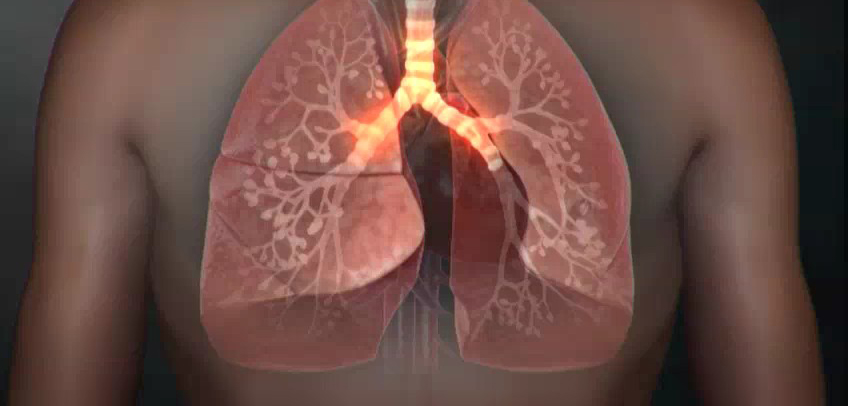

폐렴 증상 4. 흉통(가슴 통증)

- 폐렴으로 인한 염증이 흉막까지 퍼지면 날카로운 가슴 통증이 발생

- 숨을 깊게 들이쉴 때나 기침할 때 통증이 심해지는 특징